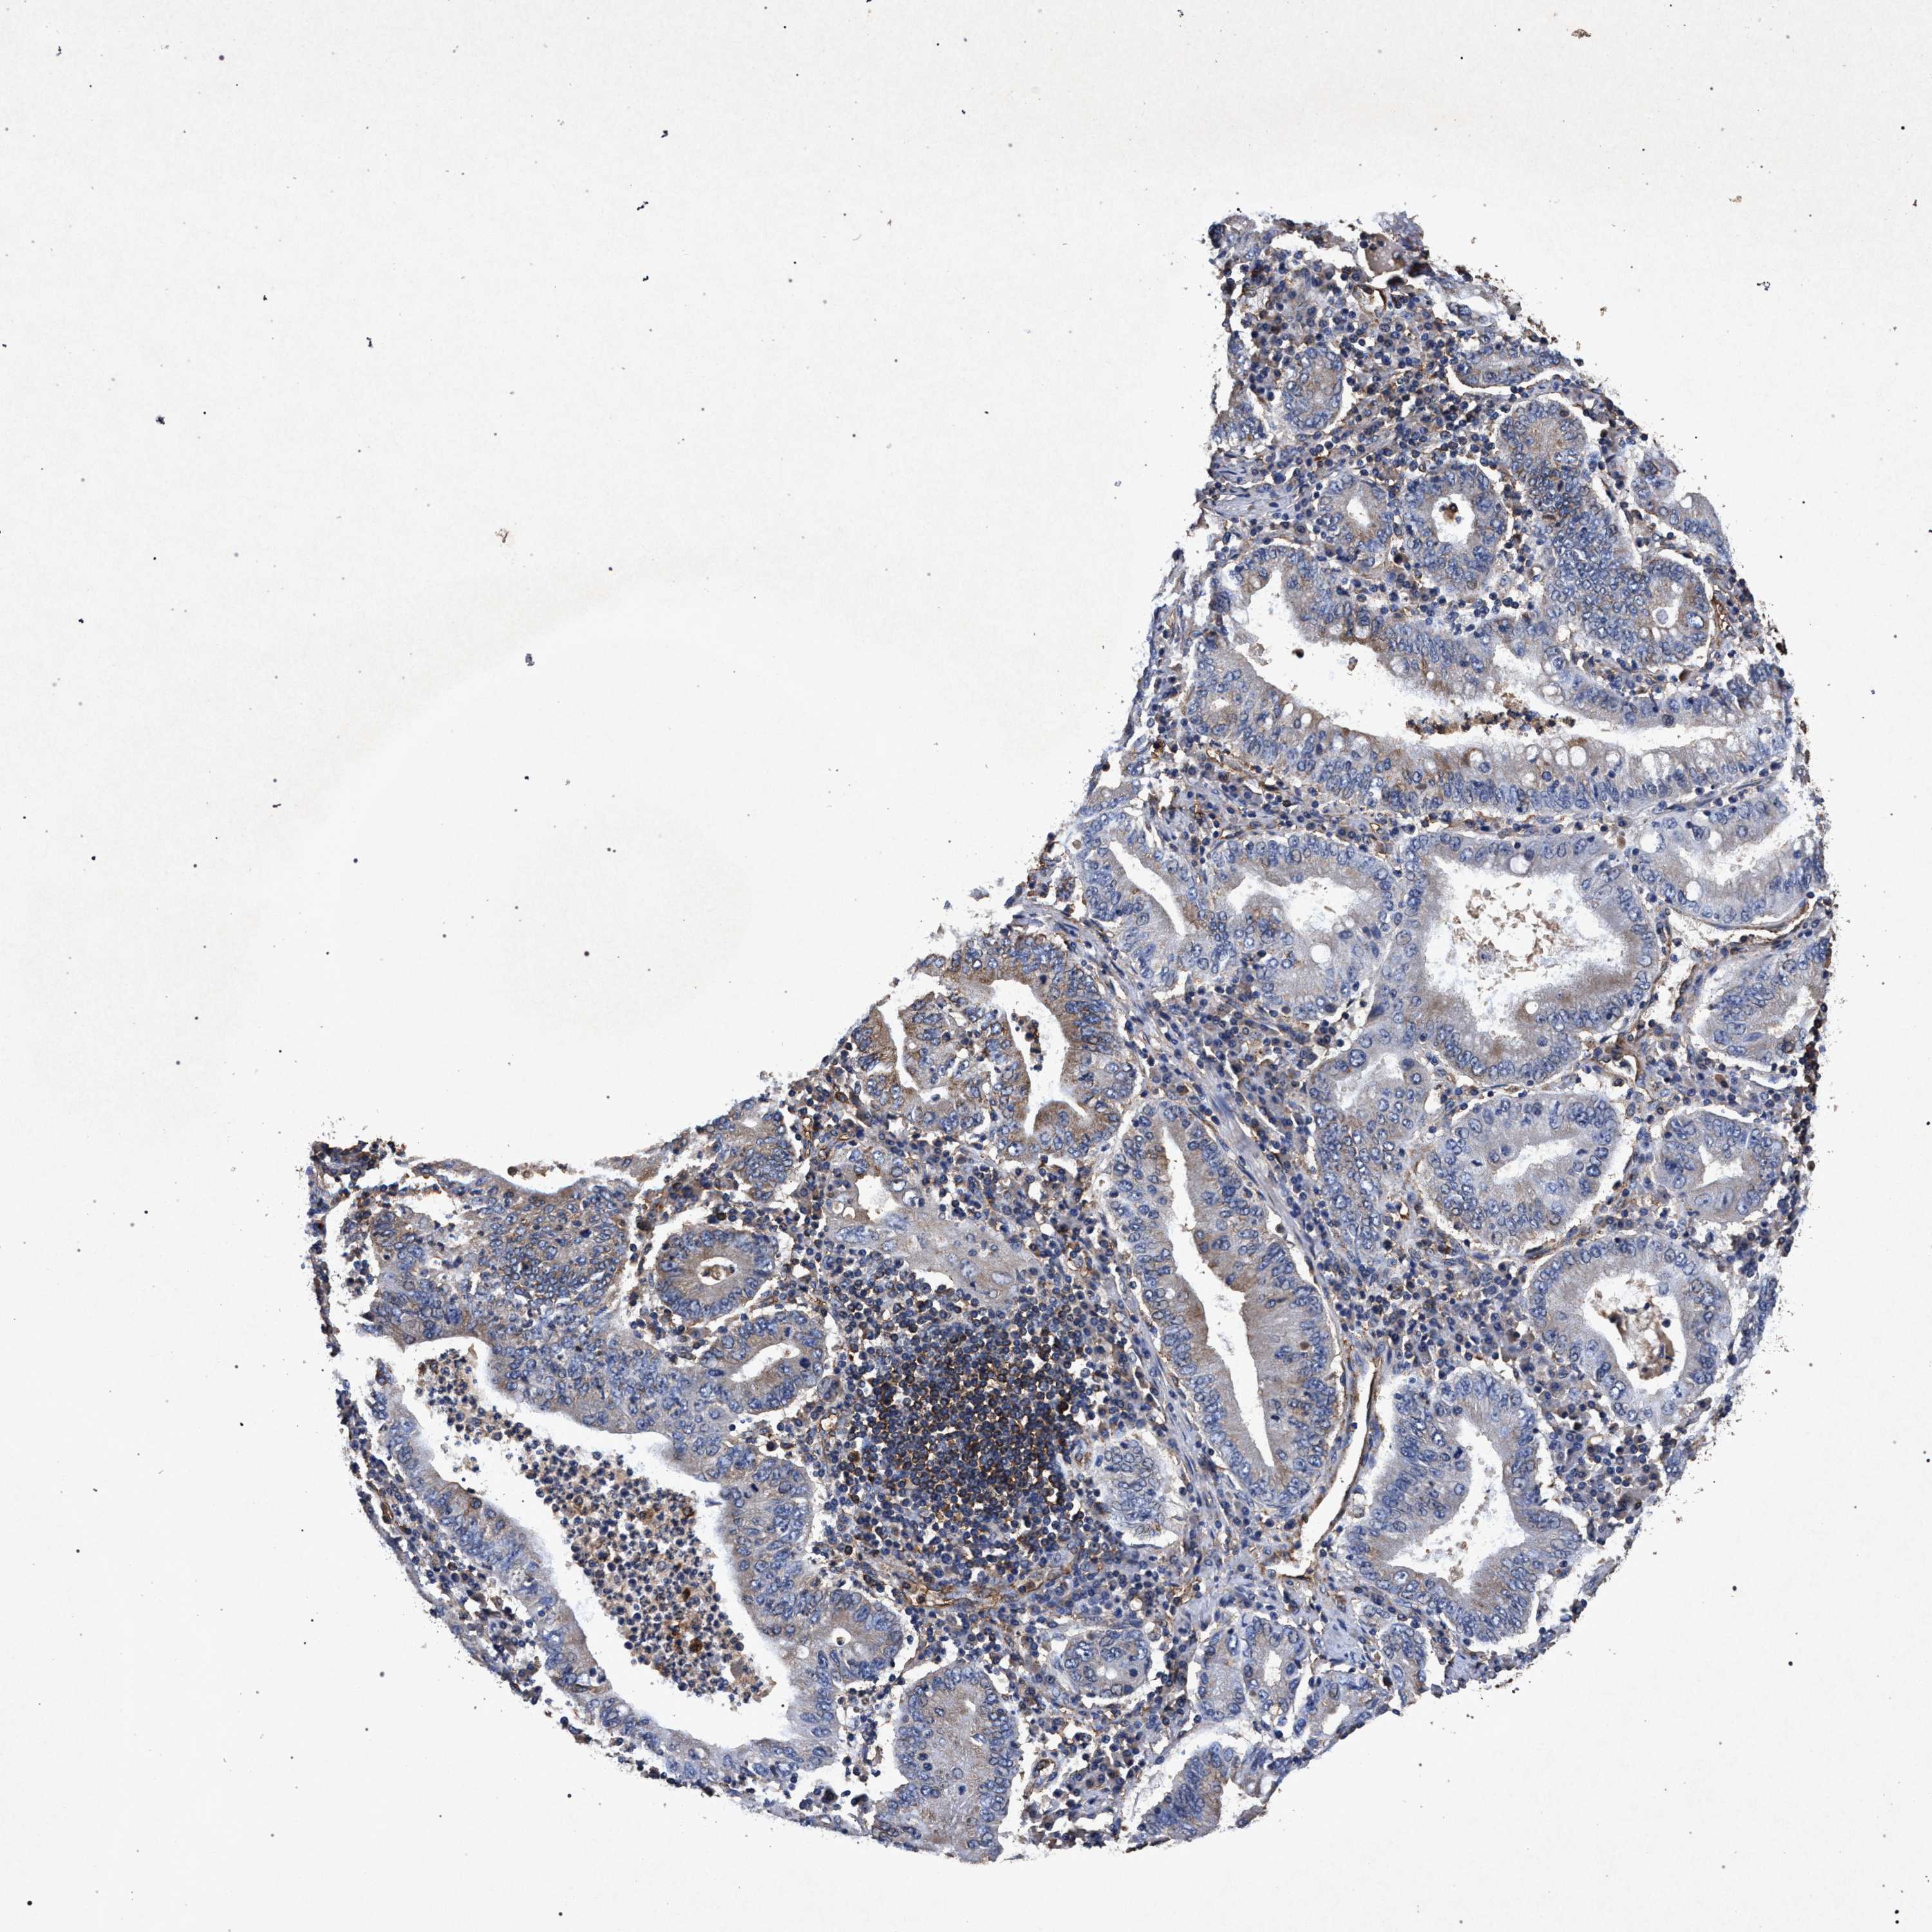

STOMACH CANCER - Protein expressioni

A mouse-over function shows sample information and annotation data. Click on an image to view it in a full screen mode. Samples can be filtered based on level of antibody staining by selecting one or several of the following categories: high, medium, low and not detected. The assay and annotation is described here.

Antibody stainingi

Antibody staining in the annotated cell types in the current human tissue is reported as not detected, low, medium, or high, based on conventional immunohistochemistry profiling in selected tissues. This score is based on the combination of the staining intensity and fraction of stained cells.

Each image is clickable and will lead to virtual microscopy that enables deeper exploration of all samples and also displays staining intensity scores, fraction scores and subcellular localization as well as patient and tissue information for each sample.

Antibody CAB022062

Adenocarcinoma, NOS

Adenocarcinoma, High grade